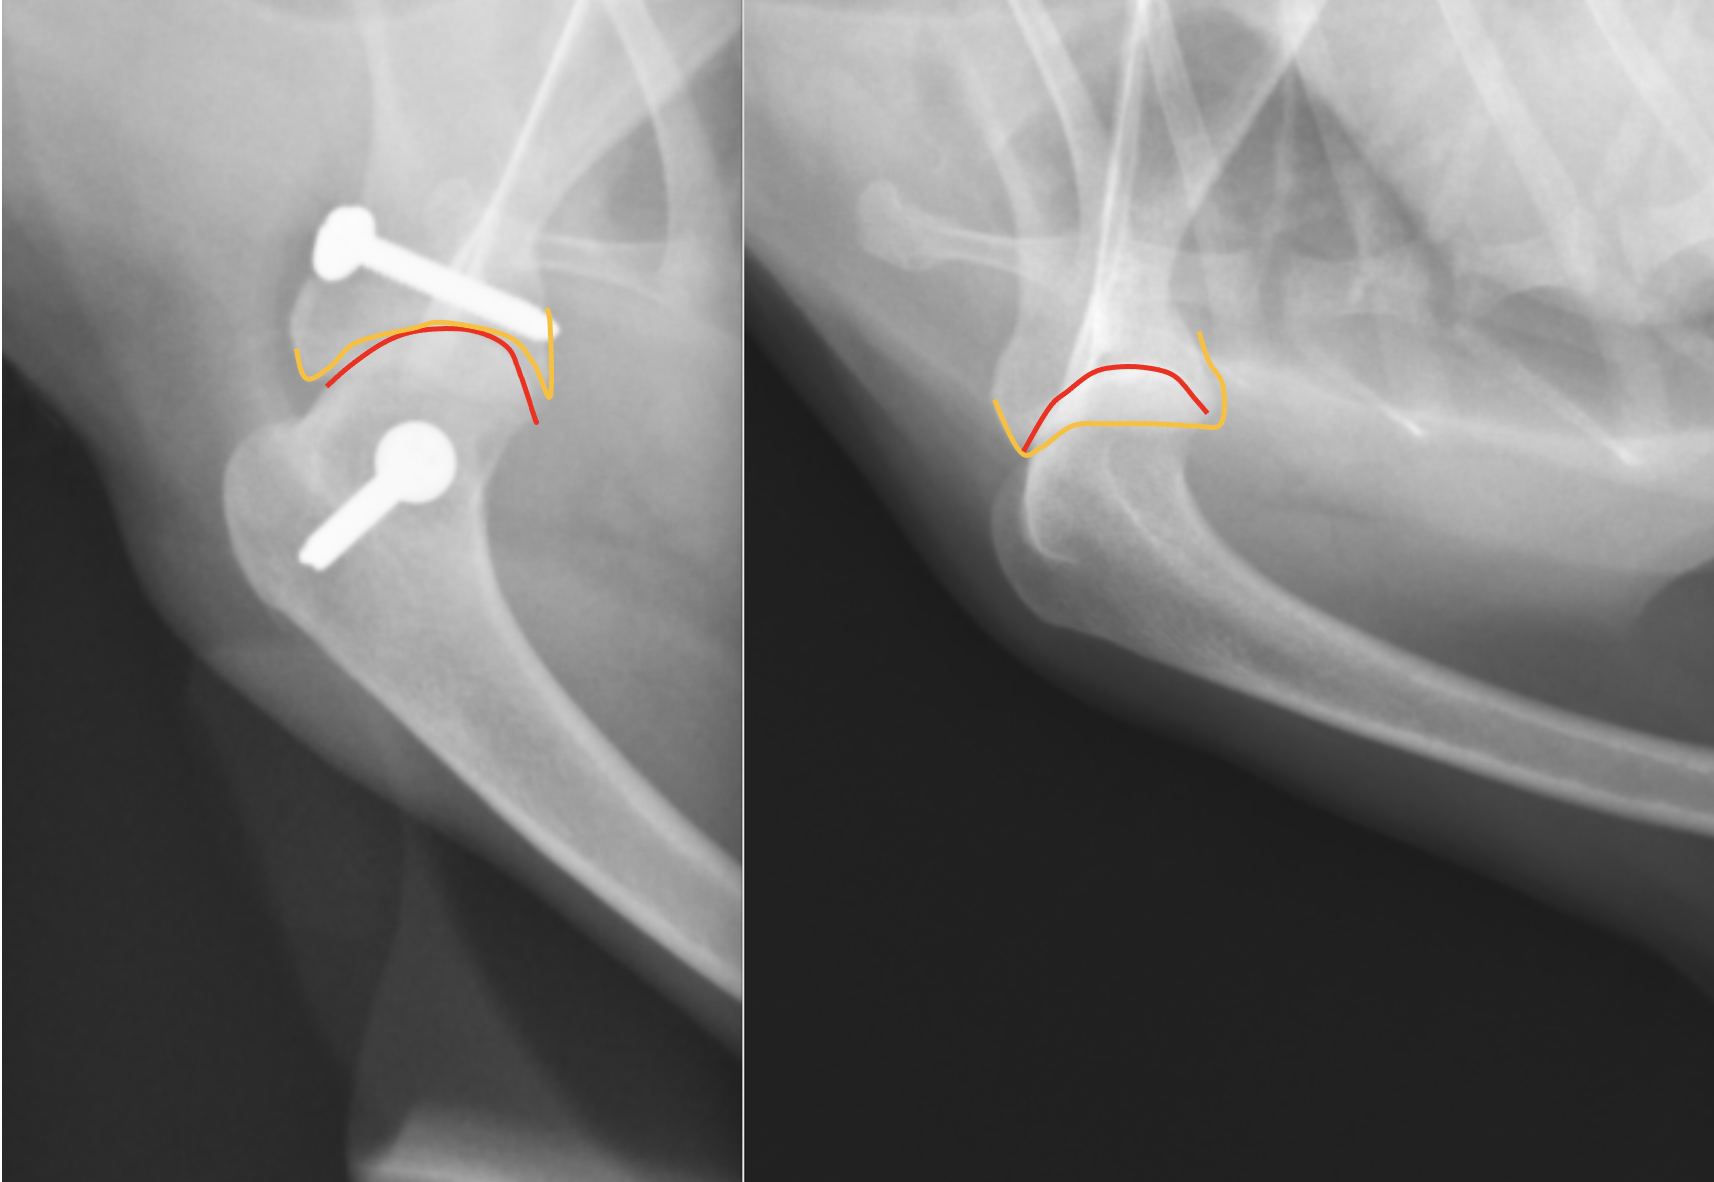

別の症例です。右が術前、左が術後のレントゲンです。分かりやすく肩甲骨と上腕骨に線を引くと・・・・

オレンジのラインが肩甲骨で、赤いラインが上腕骨頭です。右の術前は全くあっていなかった関節が、左の術後にはピッタリとあっているのがわかると思います。今回は前回のスクリューにプラスして、肩甲骨にもアンカーを入れ、糸による靭帯の強化をおこなっています。